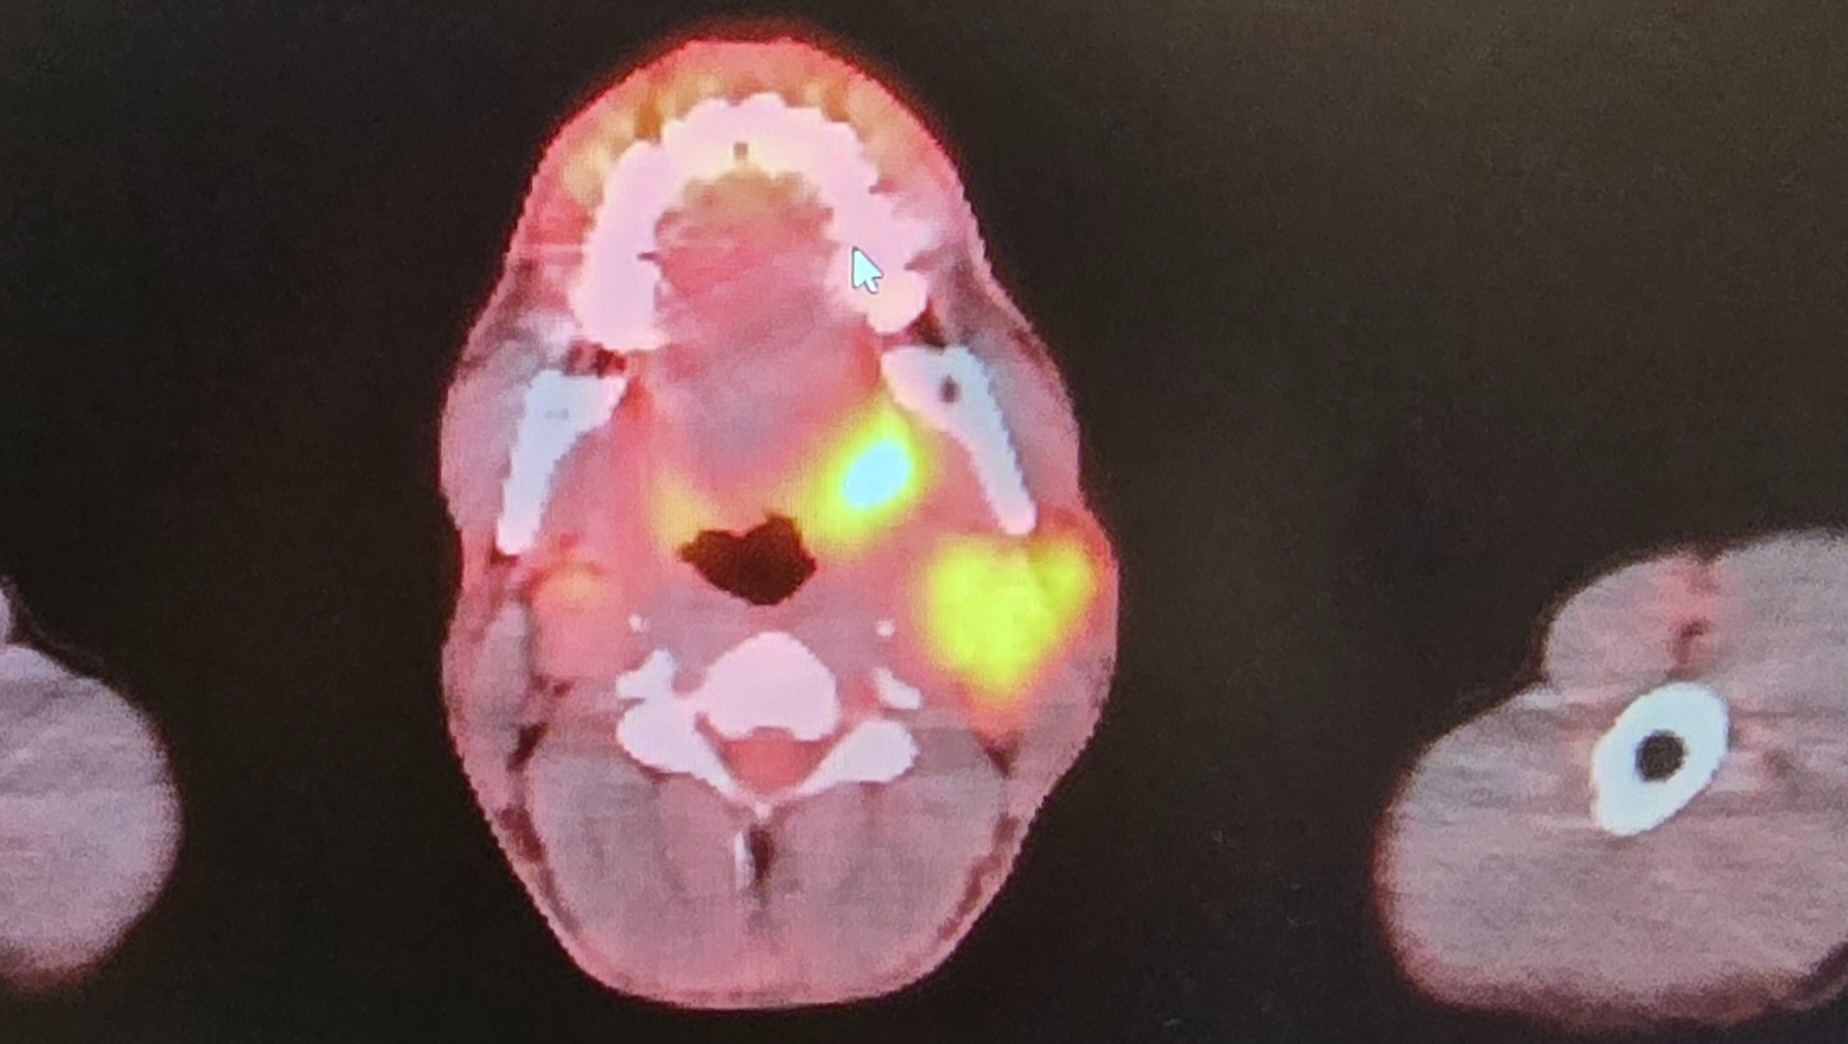

My name is Shane, and on October 30th, I was diagnosed with metastatic poorly differentiated non keratinizing squamous cell carcinoma. Since then, my life has changed dramatically. I am currently undergoing weekly chemotherapy and daily radiation treatments, which has made it impossible for me to work. The physical and emotional toll of treatment is challenging, and the uncertainty about my health and future can feel overwhelming at times.